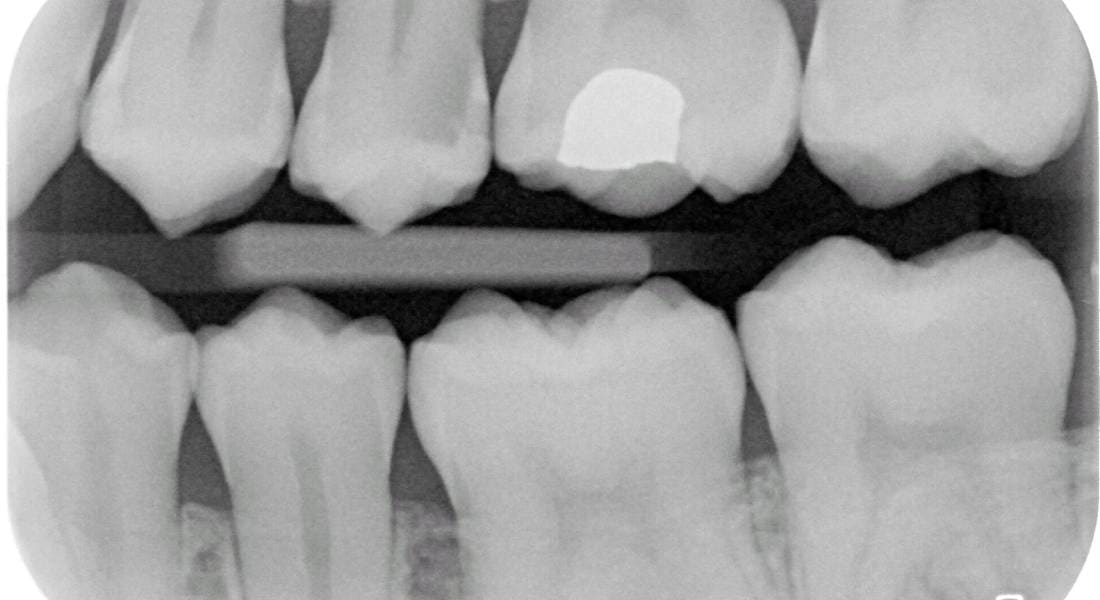

>>331450676 может он полуслепой, таких полно. Найди доктора у который знает что такое byte-wing снимки и/или диагнокам. Если эти штуки на приеме были и там чисто, то переживать не о чем